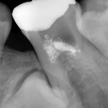

3. 左下根治前X線

やはり初診時の左側6番部です。5番が埋伏してその歯冠が6番の近心に被っています。乳歯列交換期おそらく7〜10歳位に6番を露髄させ、生切して乳歯Eを早期抜歯し、その後の保隙処置がなされなかったと思われます。

4. 左下6番根治後X線

左下5,6番部に関しては悩みました。6番が失活で不良根充です。6番のみならず埋伏している5番までダメになると思われます。埋伏歯を抜歯して6番を再根治するか?根治してもやはり失活は弱いので、6番を抜歯して5番をエクストルージョン(矯正にて引っ張り出す)するか?患者様には説明を何度も繰り返し、ご自身で選択してもらいました。歯科医任せではダメという認識が芽生えたようです。結局6番は再根治して出来るだけ保存し、ダメになるようなら抜歯して5番を引っ張り出す展望で経過観察とします。